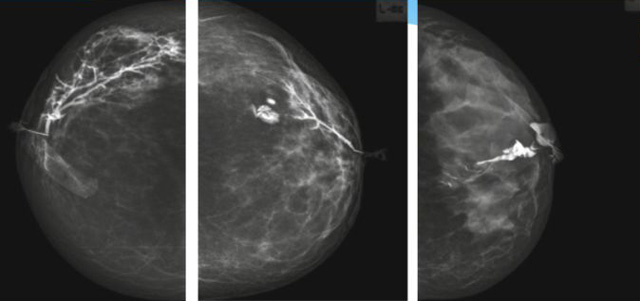

乳腺導(dǎo)管內(nèi)乳頭狀瘤分為以下兩個(gè),位于乳暈區(qū)大導(dǎo)管的中央型乳頭狀瘤,起源于末梢導(dǎo)管小葉單位的外周型乳頭狀瘤。外周型乳頭狀瘤常常沒有明顯的的臨床表現(xiàn),常因X線或乳腺超聲設(shè)備檢查發(fā)現(xiàn)。重點(diǎn)要關(guān)注的是中央型乳頭狀瘤,發(fā)生于任何年齡的女性,以40~50歲者居多。它表現(xiàn)為:單側(cè)乳頭溢液,特別是血性溢液少數(shù)病人可在乳暈區(qū)觸及腫塊。從病理學(xué)上面講表現(xiàn)為導(dǎo)管上皮和間質(zhì)增生形成有纖維脈管束的乳頭狀結(jié)構(gòu)。這是它一個(gè)病理學(xué)上的表現(xiàn)。它的超聲表現(xiàn)為:病變導(dǎo)管囊狀擴(kuò)張呈無回聲,內(nèi)可見乳頭狀低回聲或中等回聲。乳暈處的導(dǎo)管擴(kuò)張,管腔內(nèi)可見邊界清楚的,低回聲實(shí)性結(jié)節(jié)。外周型導(dǎo)管內(nèi)乳頭狀瘤可,表現(xiàn)擴(kuò)張為為低回聲的實(shí)性結(jié)節(jié),CDFI:部分腫瘤可顯示為軸心性的看到血流信號(hào)。乳腺增生癥:可見導(dǎo)管擴(kuò)張,內(nèi)無乳頭狀實(shí)性回聲,導(dǎo)管內(nèi)乳頭狀癌:囊內(nèi)乳頭狀癌病變較大,不規(guī)則,厚基底,血流豐富。以囊性為主的混合回聲,形態(tài)不規(guī)則,內(nèi)見實(shí)性低回聲實(shí)性低回聲可見少量血流,病理為囊內(nèi)乳頭狀癌。